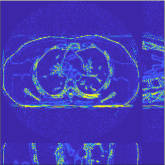

This section compares the generalization capabilities between the proposed MBIR method, PWLS-ST-, and a denoising deep NN, FBPConvNet [14], that are trained from the phantom data; in particular, we tested the trained PWLS-ST- and FBPConvNet models to phantom and clinical scan data. The results in Fig. 6 show that the non-MBIR FBPConvNet method has higher overfitting risks, compared to the proposed PWLS-ST- MBIR method. When tested on clinical scan data, PWLS-ST- achieves much more accurate reconstruction, compared to FBPConvNet. See Fig. 6(b). When tested on phantom data, FBPConvNet generates more unnatural features as the number of views reduces, although it gives lower RMSE values compared to PWLS-ST-. See zoom-ins in Fig. 6(a). The FBPConvNet results above correspond to those in the recent work [16] that FBPConvNet [14] generated some unexpected structures.